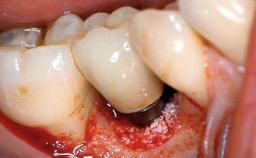

Biological complications caused by undetected cement residue have been receiving much attention. Excess cement might be responsible not only for rapidly developing of peri-implantitis, but also for delayed or chronic manifestations of the disease many years after cementation (Wilson 2009; Linkevicius and coworkers 2013). Invitro and clinical studies have shown that it is very difficult or even impossible to completely clean up excess cement at subgingival margins, so popular in cemented restorations (Agar and coworkers 1997; Linkevicius and coworkers 2011, 2012). Possible outcomes of biological complications due to excess cement range from temporary inflammation of the peri-implant soft tissues without any serious esthetic and functional consequences all the way to implant loss. This report describes a case of peri-implantitis caused by residual cement; as well as the management and quite unusual resolution of the complication. The patient presented in 2009 with a draining sinus tract, tenderness on chewing, and tissue contact above the implant-supported restoration. The implant had been restored approximately three years before.